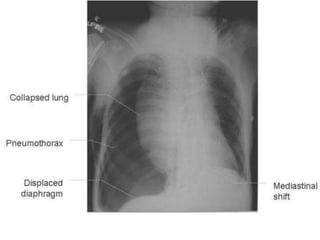

Pneumothorax

• Radiological signs:

– + shift of the heart and mediastinum to the

opposite side

– + depression or inversion the diaphragm

Tension pneumothorax

Pneumothorax • Radiological signs: –+ shift of the heart and mediastinum to the opposite side – + depression or inversion the diaphragm